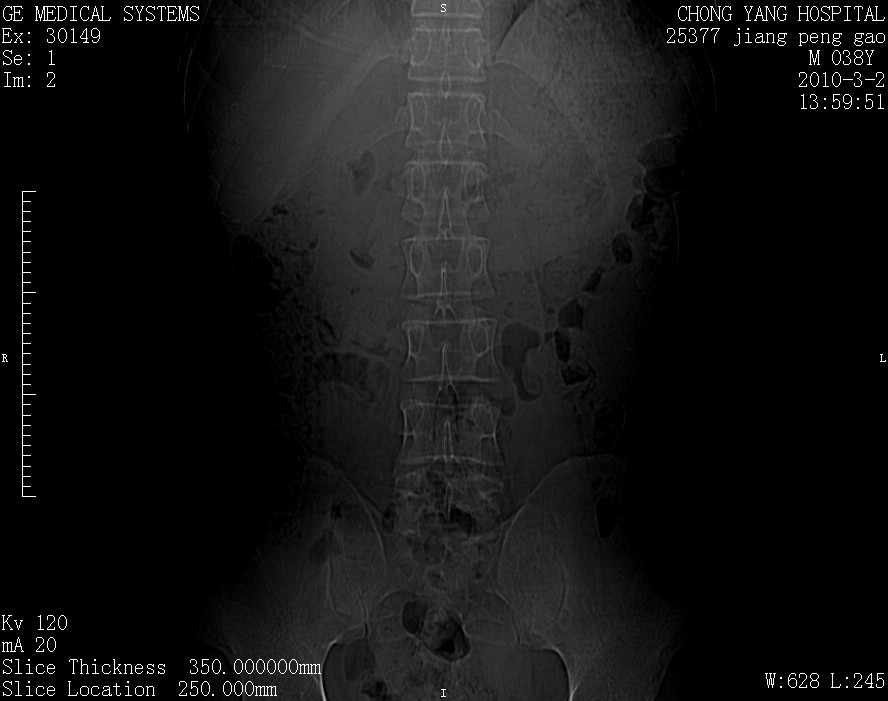

标题: CT24887:M38Y 反复腰痛 无外伤史 未做针灸 竖脊肌为何积气 [打印本页]

标题: CT24887:M38Y 反复腰痛 无外伤史 未做针灸 竖脊肌为何积气

退变,轻度增生/间盘膨出、l5椎后缘软骨结节。

肌间隙积气过多也为退变表现。